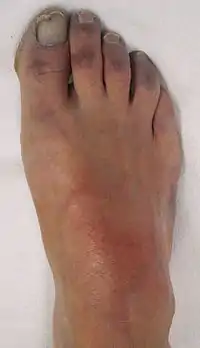

![]() Isquemia vascular en un pie mostrando cianosis. | ||

Cianosis es la coloración azulada de la piel, mucosas y lechos ungueales,[1] usualmente debida a la presencia de concentraciones iguales o mayores a 5 g/dL de hemoglobina sin oxígeno en los vasos sanguíneos cerca de la superficie de la piel,[2] o de pigmentos hemoglobínicos anómalos (metahemoglobina o sulfohemoglobina) en los hematíes o glóbulos rojos. Debido a que la cianosis depende de la cantidad y no de un porcentaje de hemoglobina desoxigenada, es mucho más fácil hallarla en estados con aumento en el volumen de glóbulos rojos (policitemia) que en aquellos casos con disminución en la masa eritrocitaria (anemia). Puede ser difícil de detectar en los pacientes con piel muy pigmentada.[3]

La cianosis se divide en dos tipos principales: la central (puede observarse mejor en los labios, las regiones malares, la lengua y la mucosa bucal, sobre todo sublingual) y la periférica (solo afecta las extremidades). La cianosis puede ocurrir en los dedos, incluyendo las uñas, además de otras extremidades (cianosis periférica) o en los labios y la lengua (cianosis central),[3] pudiendo conducir también a una inflamación del tejido conectivo en los dedos de las manos, patología conocida como dedos hipocráticos.

Aparece como resultado de la disminución del flujo sanguíneo periférico y de vasoconstricción. El flujo sanguíneo lento permite que cada hematíe esté en contacto con los tejidos durante más tiempo; en consecuencia, se extrae más oxígeno de la sangre arterial con el posterior incremento de hemoglobina reducida en la sangre venosa. Se observa habitualmente en los tejidos periféricos (manos, orejas, nariz y pies), pudiendo ser generalizada o localizada. Las causas que la originan son múltiples, entre las que se encuentran las mismas que en el caso de la cianosis central, excepto que la periférica puede observarse sin que existan problemas cardíacos o pulmonares. Los pequeños vasos sanguíneos pueden ser restringidos y se puede tratar mediante el aumento del nivel de oxigenación normal de la sangre, por el calentamiento de la zona o por elevación del miembro afectados.[8]